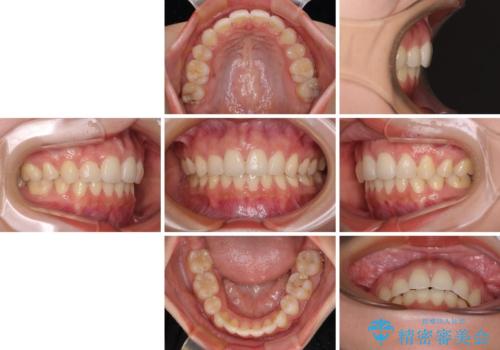

目立たない裏側装置 ハーフリンガルの抜歯矯正

- 口元の突出感を気にして来院された患者様です。

上下左右の第一小臼歯4本を抜歯して口元を下げる治療計画としました。

目立たない装置が希望であったため、上顎が裏側装置である、ハーフリンガル装置を選択されました。

3年半ほどで終わる予定でしたが、途中引っ越し、出産、引っ越し、出産を繰り返し、なかなか来院することができず、装置を外すまでに8年以上の期間がかかってしまいました。